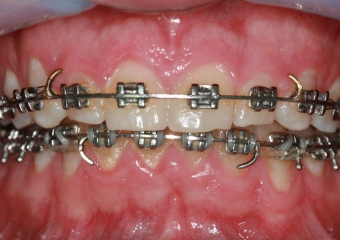

Raio X inicial